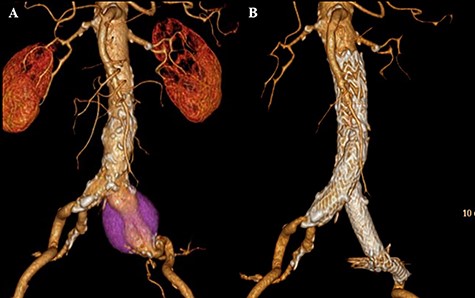

CT scan showing the increasing sac size of left CIAA with no endoleak (A) and aortic replacement with a Y-shaped vascular prosthesis performed with complete explantation of the endograft (B).

The infrarenal aorta up to the right common iliac artery and the left external iliac artery were exposed via a retroperitoneal approach. Proximal control was achieved by clamping midway between the renal arteries and the aortic bifurcation, and distal control was achieved by inserting an occlusion balloon into the right common iliac artery and clamping the left external iliac artery. The sac of the CIAA was opened, and many thrombi were noted around the stent graft. No backbleeding of the lumbar arteries or junctional bleeding of the stent was detected, and the entire endograft was removed easily. Abdominal aortic replacement with a Y-shaped vascular prosthesis (J Graft SHIELD NEO, bifurcated vascular prosthesis) was performed (Fig. 2B). Proximal and distal anastomoses were performed at the level of midway between the renal arteries and the aortic bifurcation where the endograft was fixed, and at the level of the right common and left external iliac arteries, respectively.